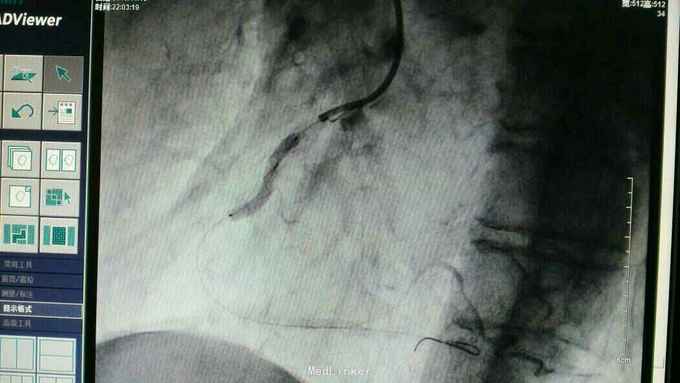

急性下壁心肌梗死,立即启动绿色通道,行急诊冠脉造影明确冠脉病变,必要时PCI治疗,行CAG示:LAD中重度狭窄,LCX尚可,RCA中段局限重度,可见前向血流,选段后降支处重度狭窄,血管钙化明显。考虑此次靶血管为RCA中段处,血管钙化迂曲明显,拟处理RCA,术中导丝到达远端后,预扩球囊反复高压扩张后,支架均无法通过,采用双导丝增加支撑依然无法通过,再更换高压后扩球囊高压扩张,锚定等,最终成功植入支架

急性心梗有时候处理相对较容易,但此病变在于血管钙化迂曲明显,且再次详细阅片后发现局部有“礁石”样病变,预扩球囊及后扩球囊不易扩张,有时需切割或旋磨,但对于急性心梗,如果血流达到理想级别,可不勉强处理,急性心梗中,有些病变为固定狭窄基础上急性血管闭塞,处理并非如一般血栓病变那样容易,造影后仍然需要详细阅片,根据具体病变情况选择合适手术处理方法